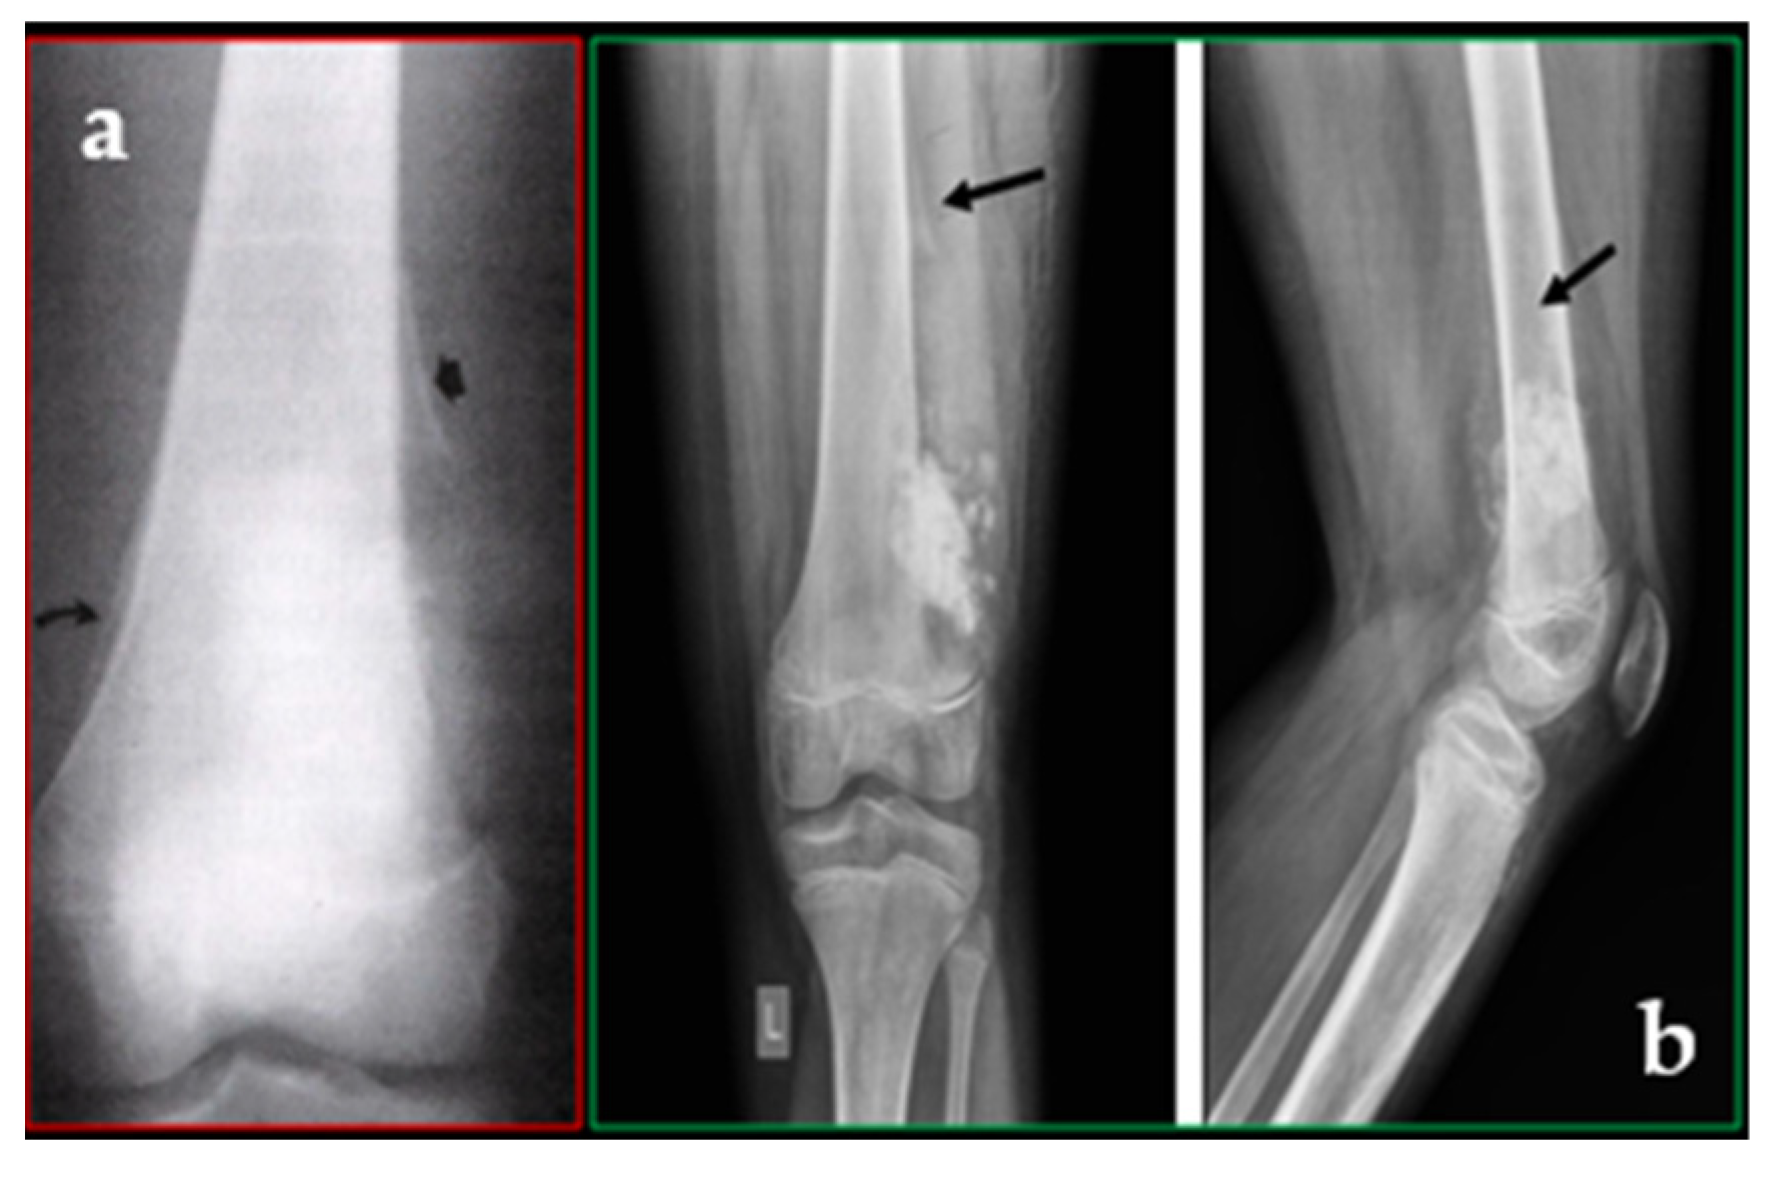

Figure 6. (a) There is ill-defined lucency in the distal femur, along with an onion-skin periosteal reaction and a broad zone of transition. (b) Humerus X-ray showing cortical erosions, bone loss, and a poor transition to normal bone. In this instance, the centre of the tumour seems to be a sunburst because of perpendicular spiculations. The tumour’s edge, which is not noticeable in this instance, has a laminated appearance that resembles onion skin. Bone sclerosis is rare. There is no distinct soft tissue mass in this instance. Radiopaedia.org.

A broad zone of transition and a lamellated/speculated periosteal reaction are characteristics of lesions that are usually aggressive, destructive, or moth-eaten (Figure 6a,b).

Radiologically, the most common form is characterised by multiple osteolytic areas, ranging from small to non-confluent foci. If the compact bone is affected, it may appear “flaky” due to progressive lamellar dissociation and, in advanced stages, it can disappear.

Frequent (58–84%) and generally violent (94%) periosteal response frequently appears as either spiculated or lamellated (“onion-skin”), (“sunburst” or “hair-on-end”).